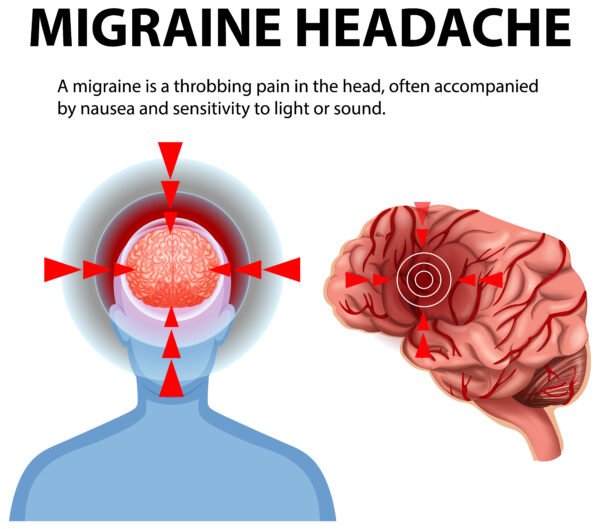

- Headache